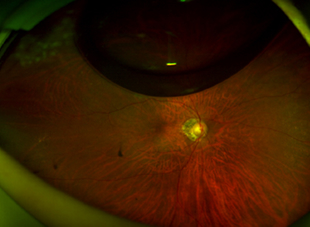

망막박리

망막박리 사진